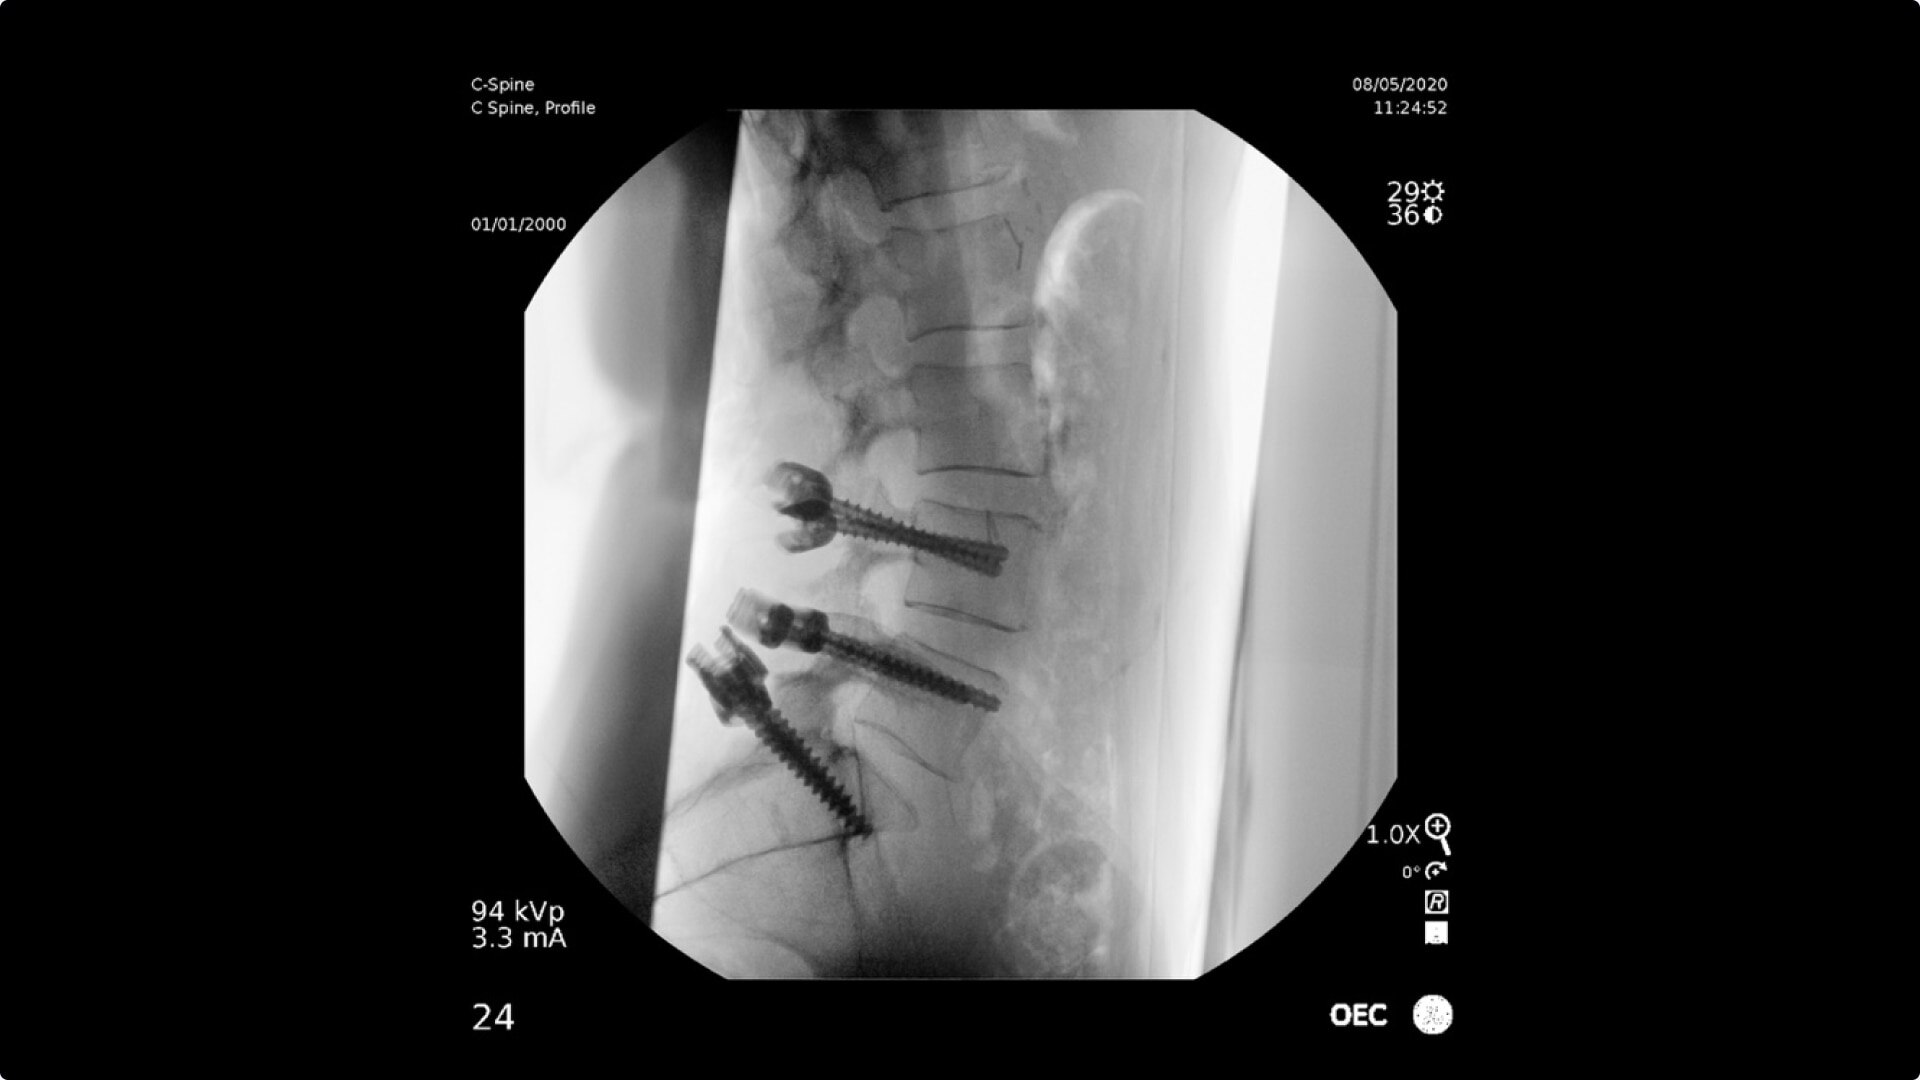

Consistently experience amazing image quality, precision, and efficiency during simple to complex pain management procedures with OEC C-arms.

Achieve precision and efficiency while experiencing the image quality needed during simple to complex pain management procedures with OEC C-arms.

OEC C-arms perform imaging in a variety of procedures such as:

• Steroid injections

• Radiofrequency treatments

• Contrast media injections

• Cervical spine pain management

• Thoracolumbar procedures